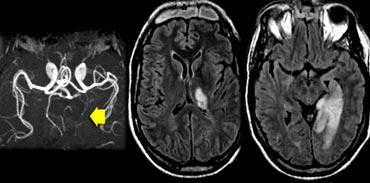

Các hình ảnh cho thấy bệnh nhân có nhồi máu PCA chiến lược liên quan đến hồi hải mã.

Loại nhồi máu này có thể dẫn đến sa sút trí tuệ đột ngột nếu nằm ở bán cầu ưu thế.

Thường sẽ không dẫn đến sa sút trí tuệ nếu xảy ra ở bán cầu không ưu thế.

Các nhân trong của đồi thị đóng vai trò quan trọng trong trí nhớ và học tập.

Nhồi máu một bên lớn hoặc nhồi máu hai bên ở vùng này có thể gây sa sút trí tuệ.

Cần chú ý đặc biệt đến các vùng này để phát hiện những ổ nhồi máu nhỏ này.

Trên hình ảnh FLAIR, bạn sẽ dễ dàng bỏ sót các ổ nhồi máu này, vì chúng có thể đồng tín hiệu với các cấu trúc xung quanh (8).

Cần có chuỗi xung T2W độ phân giải cao để phát hiện các ổ nhồi máu đồi thị này.